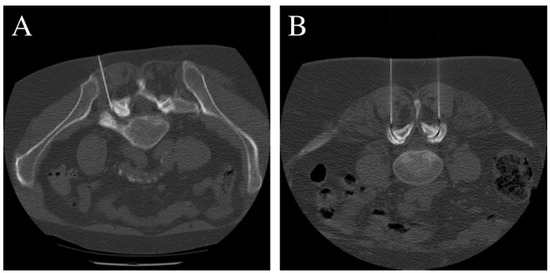

2.4. Intervention